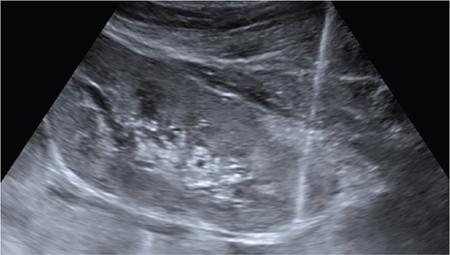

NONVASCULAR RENAL INTERVENTION Amitha Vikrama Nonvascular renal interventions have come a long way and have significantly reduced the surgical mortality and morbidity. It also paves way for short hospital stay and thus reducing the chances of nosocomial infection. They are usually pinhole or keyhole procedures with less distortion of the anatomy and physiology. They vary from image-guided aspiration/biopsy to percutaneous nephrostomy to complex procedures like ureteric stenting, strictureplasty, percutaneous nephrolithotomy etc. Iversen and Brun were the first to perform percutaneous renal biopsy of native kidneys in 1951. Over the years, newer imaging and biopsy techniques have evolved which have increased the biopsy yield to >95% and significantly reduced the complications of renal biopsy, resulting in decreased mortality rates from 0.12% to 0.02% during the last 50 years NOTE: Solitary renal mass lesions suspicious for malignancy should not be subjected to percutaneous biopsy, as there are chances of tumour seeding along the biopsy track. Excision biopsy is preferred for those lesions as it can be curative. USG-guided renal biopsy is the preferred method over blind biopsies. It avoids nontarget biopsies and reduces bleeding risks. Usually the lower pole of the kidneys is preferred site in native renal biopsy. The needle has to be directed into the lower cortex and care taken to avoid renal medulla and collecting system. 18G trucut biopsy needles are usually used in adults. In paediatric population, 20G can be used. Rarely, Coaxial technique is used in very obese patients and in those who are unable to lie prone. It is usually done as an inpatient procedure. Four hours of fasting is required to prevent aspiration of gastric contents during the procedure. Antiplatelets and anticoagulants are stopped at least 3–5 days prior. Informed written consent has to be taken after explaining the risks and benefits of the procedure. Patient is to be positioned in prone and USG-guided marking of the site of biopsy done prior to cleaning and draping. The depth of the renal cortex from the skin surface has to be noted. If the ribs are coming in line with the lower pole cortex, then a cranially angulated path is preferred. After infiltration of 2% lignocaine, the biopsy needle is advanced up to and not into the lower pole cortex. As the kidney keeps moving with respiration, the biopsy should be properly timed to avoid hitting the collecting system and medulla. This method is real-time ultrasound guided renal biopsy (Fig. 10.21.1.1). There is another method practiced in few of the institutes where the location of lower pole of the kidney is marked on the skin after ultrasound screening. The marking corresponds to the lower most renal cortex at the end of normal inspiration and the biopsy path will be perpendicular to the bed without any craniocaudal or mediolateral angulation. The distance between the skin and the renal cortex is measured. The patient will be instructed strictly not to change his position. Then the biopsy will be done blindly without any real time USG guidance. With this method, more number of patients can be biopsied in a short interval time. In a transplanted kidney, which is usually grafted in the iliac fossa, biopsy can be obtained from upper or lower pole. Points to remember: Cortical tangential and cortical non tangential approaches have been described (Fig. 10.21.1.2). Cortical tangential approach is described to have better diagnostic yield with lesser complications. In this approach, the needle track will be almost parallel to the capsule so that only the cortical tissue is targeted (Fig. 10.21.1.3A–C). Renal biopsy can also be done with coaxial technique. In this method, a coaxial needle, one size bigger than the biopsy needle, usually 17G, is inserted up to the renal capsule. The stylet is then removed and the 18G biopsy needle is inserted through the coaxial needle and the required number of biopsy specimens obtained. After this, the rent in the capsule can be sealed off with gelatine plugs before removing the coaxial needle. This helps in preventing bleeding complications. In patients with high risk of bleeding due to coagulation abnormalities, transjugular renal biopsy can be done in which renal vein is cannulated and biopsy done from within (Fig. 10.21.1.3D–F). In obese patients who cannot lie prone, biopsies are done in lateral or oblique lateral positions under CT or USG guidance. CT guidance is especially helpful when the visualization of the kidney is difficult on ultrasound. In these cases, coaxial technique is always helpful. In 2019, KHA-CARI guidelines were first published for renal biopsy. A few of the salient recommendations are given below: It is an image-guided procedure in which the renal pelvicalyceal system is accessed percutaneously which is predominantly used for decompressing an obstructed system and also for various other therapeutic procedures. It is usually done under local anaesthesia and IV sedation. Major procedures might require general anaesthesia. All routine preprocedural blood tests and coagulation profile should be done. Appropriate antibiotics are administered intravenously prior to the procedure. 21G needle, 018 and 035 wires, appropriate dilators, sheath and pigtail drainage catheter. Ultrasound and fluoroscopy is required for guidance. Patient is usually positioned prone on the table. Under special circumstances, lateral or oblique positions are also used. After instillation of local anaesthesia, a 21G needle is used to access the renal calyx under USG guidance. Once the urine flow is seen, nonionic contrast is injected to delineate the renal collecting system. A 018 wire is passed through the needle into the pelvicalyceal system and later exchanged for a 035 wire. Appropriate tissue dilators are used to dilate the track before placing a pigtail drainage catheter. The drain is secured by stay sutures and connected to a urobag. The initial urine sample is to be sent for culture and sensitivity (Figs. 10.21.1.4–10.21.1.6). Ureteric stenting was first described by Zimskind et al endotracheal tube al in 1967. It is one of the commonest procedure done in urology practice It is usually done after doing a percutaneous nephrostomy. The percutaneous nephrostomy (PCN) drain is replaced with a 6F or 8F sheath over a guidewire and ureterogram is obtained to assess the site of stricture or obstruction. Using a catheter and guide wire combination, the stricture is negotiated and the exchange length hydrophilic wire is parked in the bladder. The ureteric length is measured and appropriate-sized double J (DJ) stent is inserted over the wire. Care is taken to get the loops formed at both ends of the DJ stent so that stent migration is prevented (Fig. 10.21.1.7). A variety of delivery systems are available for the deployment of the ureteric stent exist: pusher mechanism, string release and sheath (similar to an inferior vena cava (IVC) filter). Post stent insertion, the nephrostomy drain can be retained for a couple of days. The drain is closed externally and USG screening is done the next day to confirm antegrade flow after which the drain can be removed.